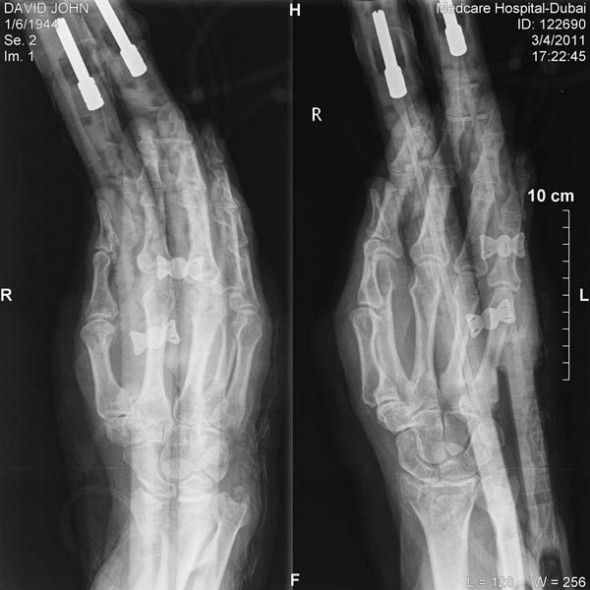

02 X-ray with Flexi kite handles holding wrist in place